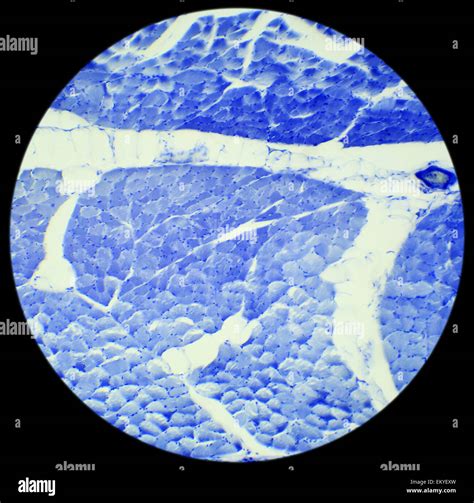

Observing Smooth Muscle Cells Under a Microscope

Once the samples are prepared, they can be observed under the appropriate microscope. Here are some key observations to look for:

• Cell Shape: Smooth muscle cells appear spindle-shaped with tapered ends.

• Nucleus: The nucleus is centrally located and appears oval or elongated.

• Cytoplasm: The cytoplasm contains actin and myosin filaments, which are responsible for contraction.

• Organelles: Various organelles, such as mitochondria and endoplasmic reticulum, are visible and play roles in cellular metabolism and protein synthesis.